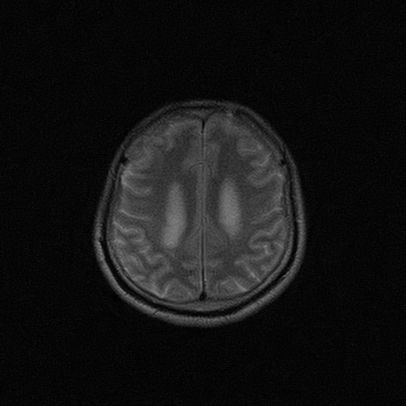

标题: MRI2064:少见病例。男性52,视力下降多年。 [打印本页]

标题: MRI2064:少见病例。男性52,视力下降多年。

四脑室区见混杂信号占位影,脑室系统扩张明显,临近结构显著受压称位,患者52岁,多考虑室管膜瘤可能性大

考虑第四脑室室管膜瘤并阻塞性脑积水。

考虑第四脑室室管膜瘤并梗阻性脑积水;部分性空蝶鞍;左侧上颌窦粘膜下囊肿。

考虑第四脑室室管膜瘤【血供丰富血管母细胞瘤可能】并梗阻性脑积水;部分性空蝶鞍;左侧上颌窦粘膜下囊肿。

比较典型的脉络丛乳头状瘤并脑积水,鉴别小脑蚓部血管母细胞瘤。